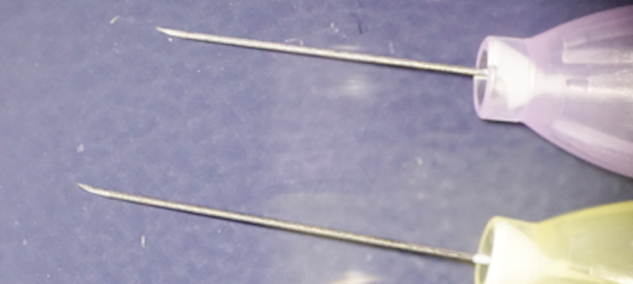

極細の注射針

麻布十番の歯医者さん・矯正歯科では今まで最細であった33Gの針を使用してきました。しかし、2020年世界最細は35Gとなり、当院ではいち早くそちらを使用していくこと

としました。

ですので、麻酔時の痛みはさらに軽減されます!

・写真上:新しい35G

・写真下:今まで使っていた33G

外径は33Gでは0.26mmでしたが35Gでは0.23mmとなっております。内径は0.11mmと、33G、35G両方変わらないのです。

外径が細くなったからといって注入圧が強くなったりということはないのです。

また、35Gは9°という鋭角な刃面加工と、シリコンコーティングにより痛みの少ない注射が

可能です。

刺通抵抗値は0.445から0.375と15%以上も低下しているようなので、その点も痛みを感じにくくなる点です。